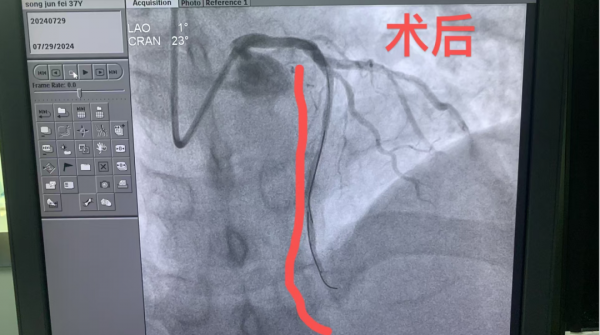

1、39歲男性,前降支閉塞,行血栓抽吸+冠脈內溶栓。